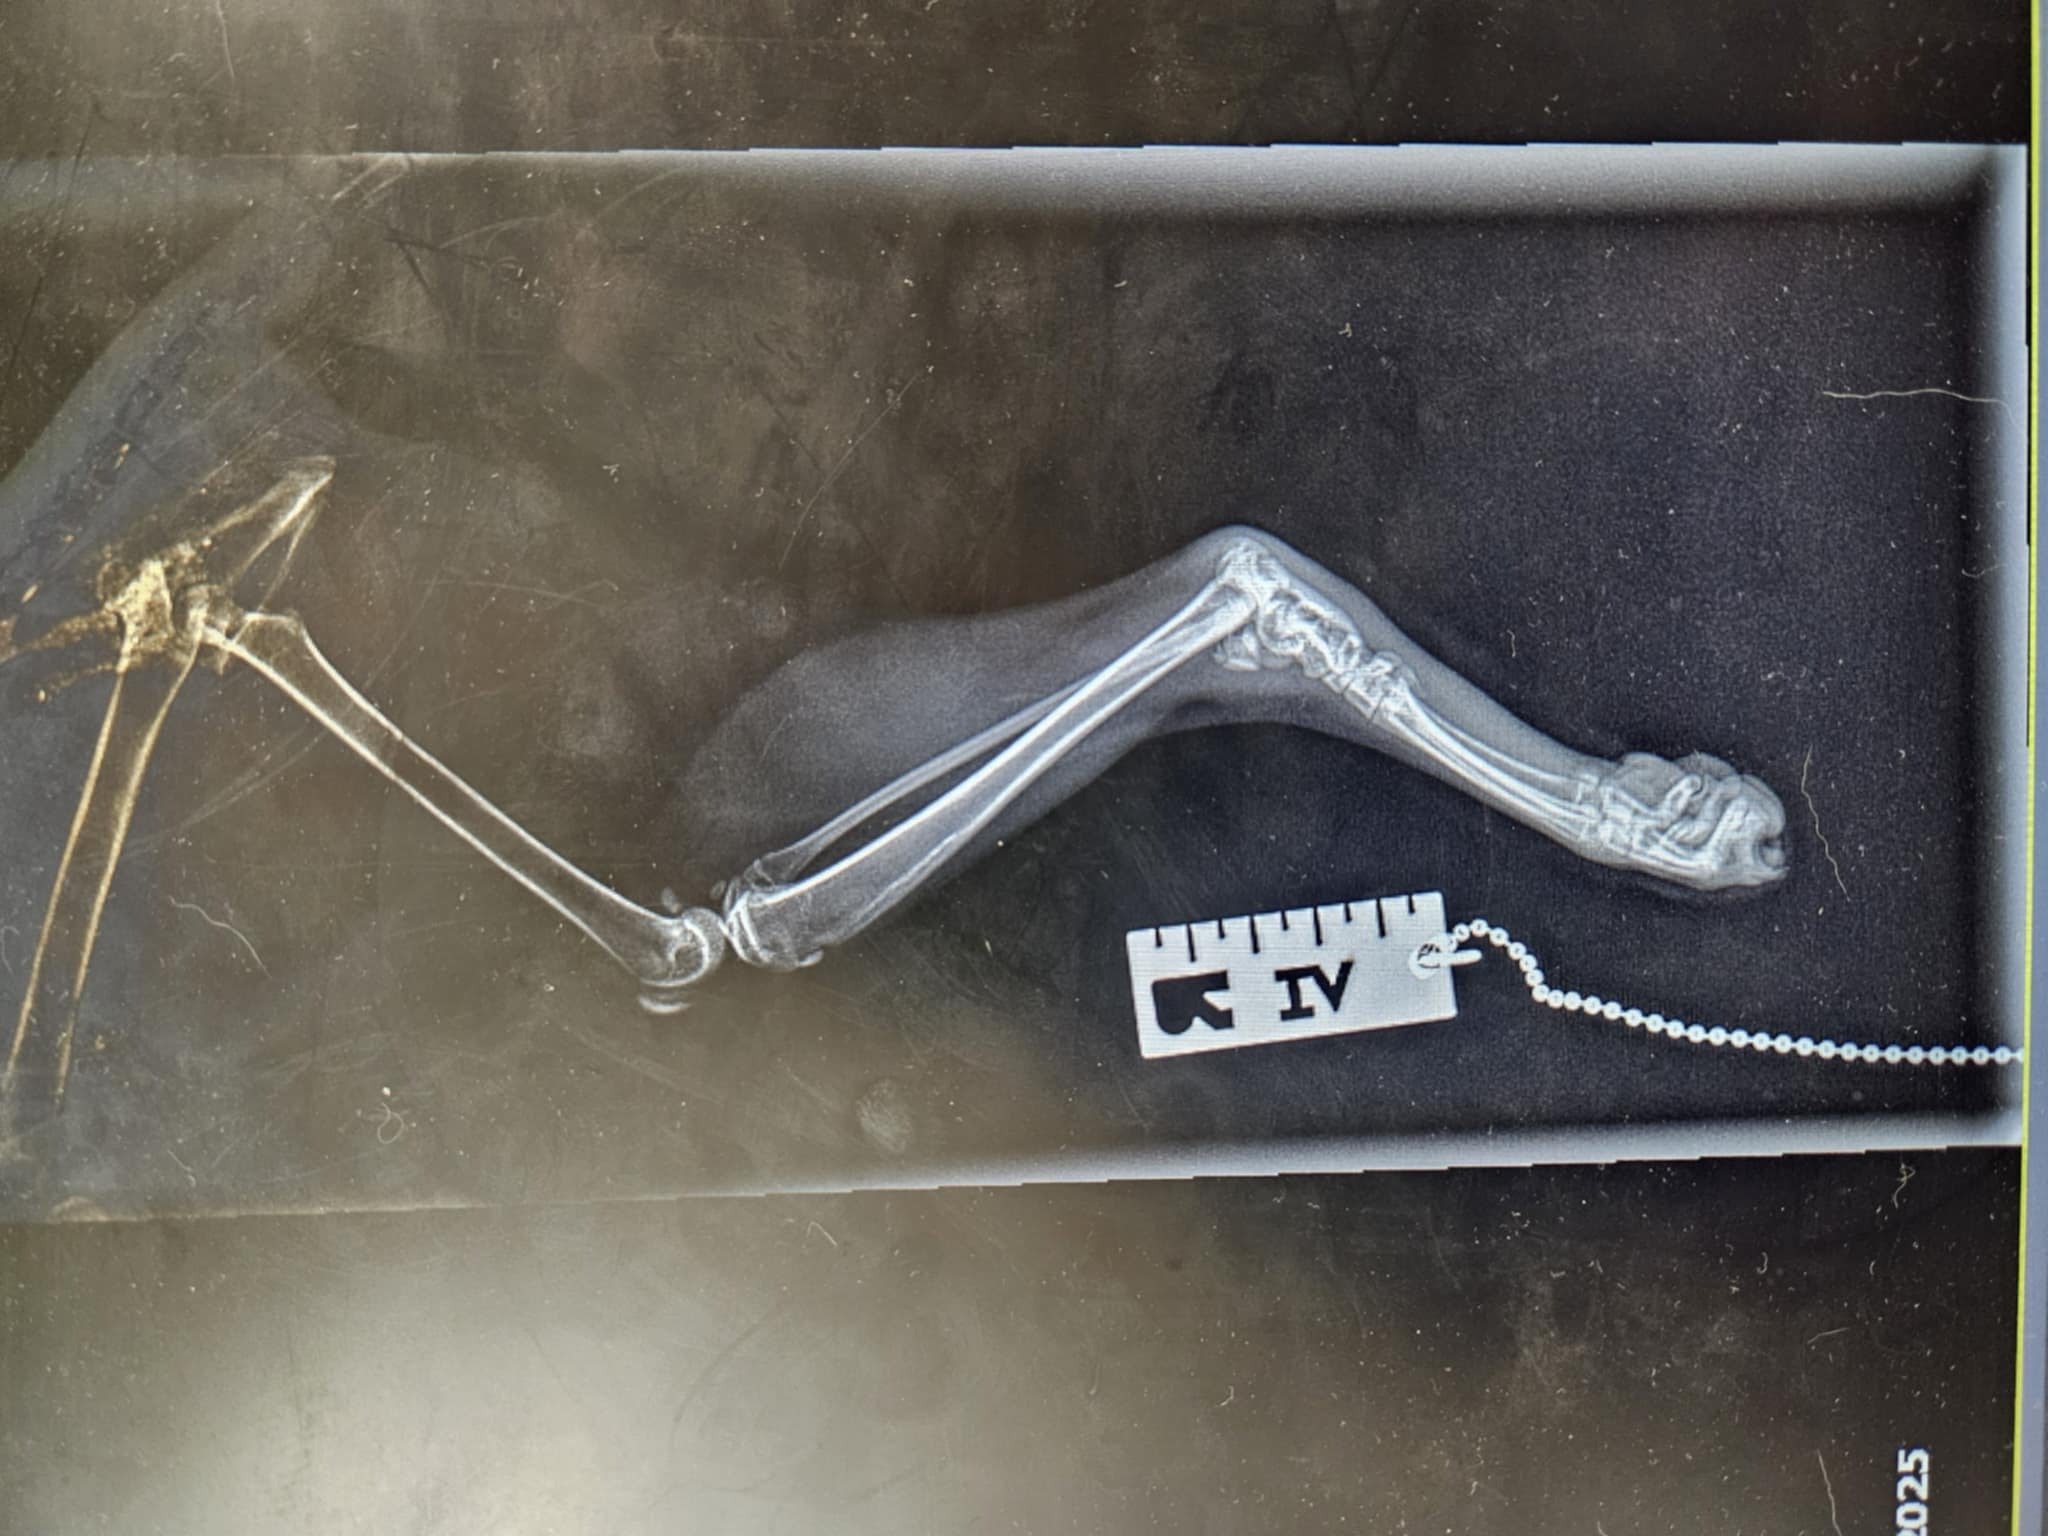

Po paru dniach Pracownicy hotelu zauważyli, że koteczka ma problem z tylną, prawą łapką. Wyraźnie kulała i powłóczyła nią.

Niestety problem z nóżką okazał się być o wiele bardziej poważny, niż "tylko" złamanie :-(.

Na najbliższy piątek, tj. 16 maja koteczka ma umówiony zabieg artrodezy,

Artrodeza jest zabiegiem operacyjnym trwale znoszącym ruchomość stawu. Artrodeza polega na usunięciu powierzchni stawowych i resekcji tkanki kostnej, a następnie stabilnemu zespoleniu kości tak, aby uległy trwałemu zrośnięciu.